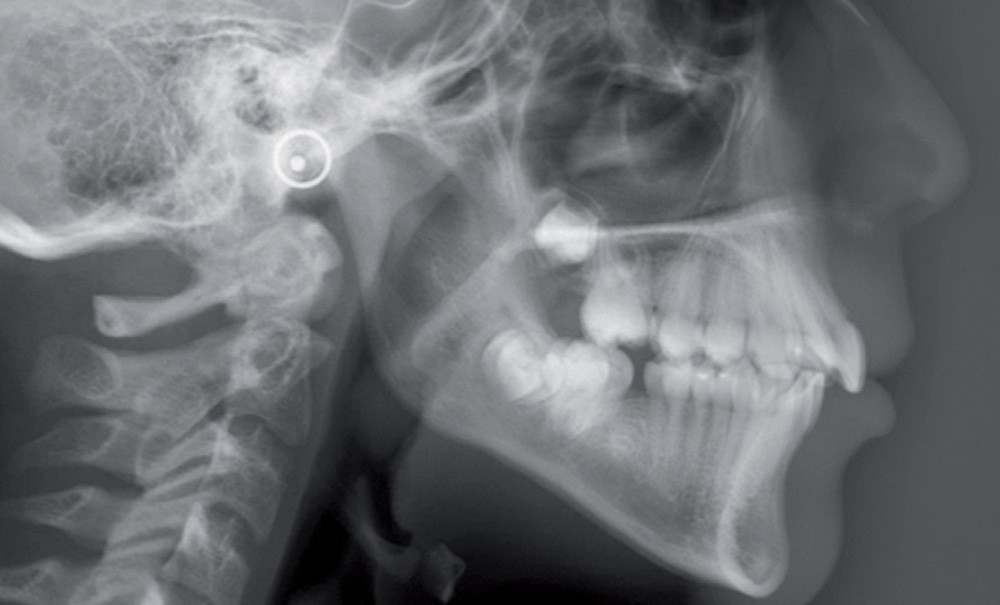

La radiographie panoramique (fig. 3a) montre l’inclinaison corono-mésiale de 17,27 et 37 et la présence des germes des quatre dents de sagesse.

La téléradiographie…